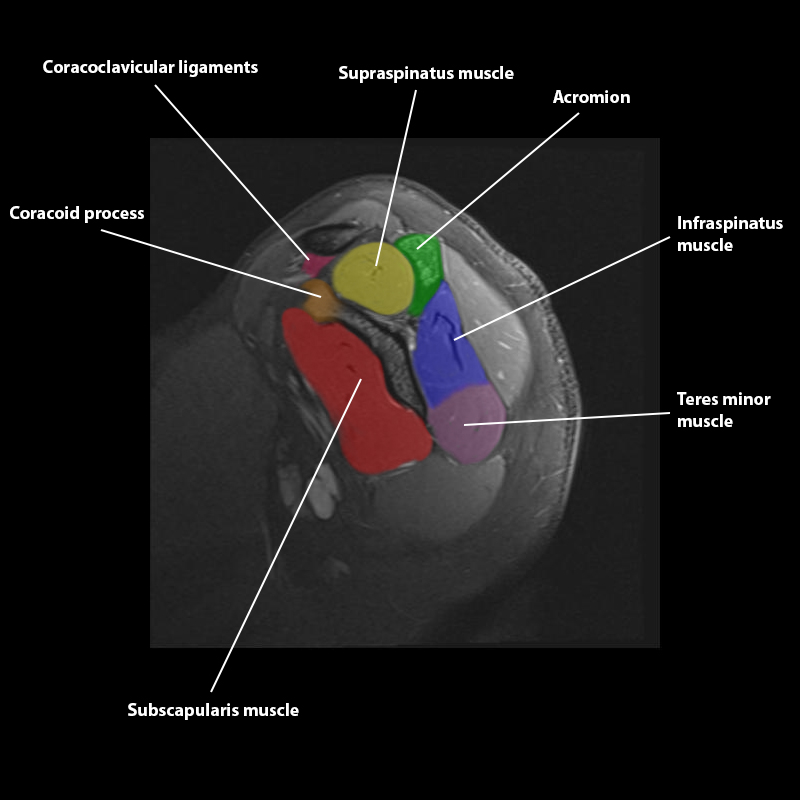

Shoulder MRI Anatomy